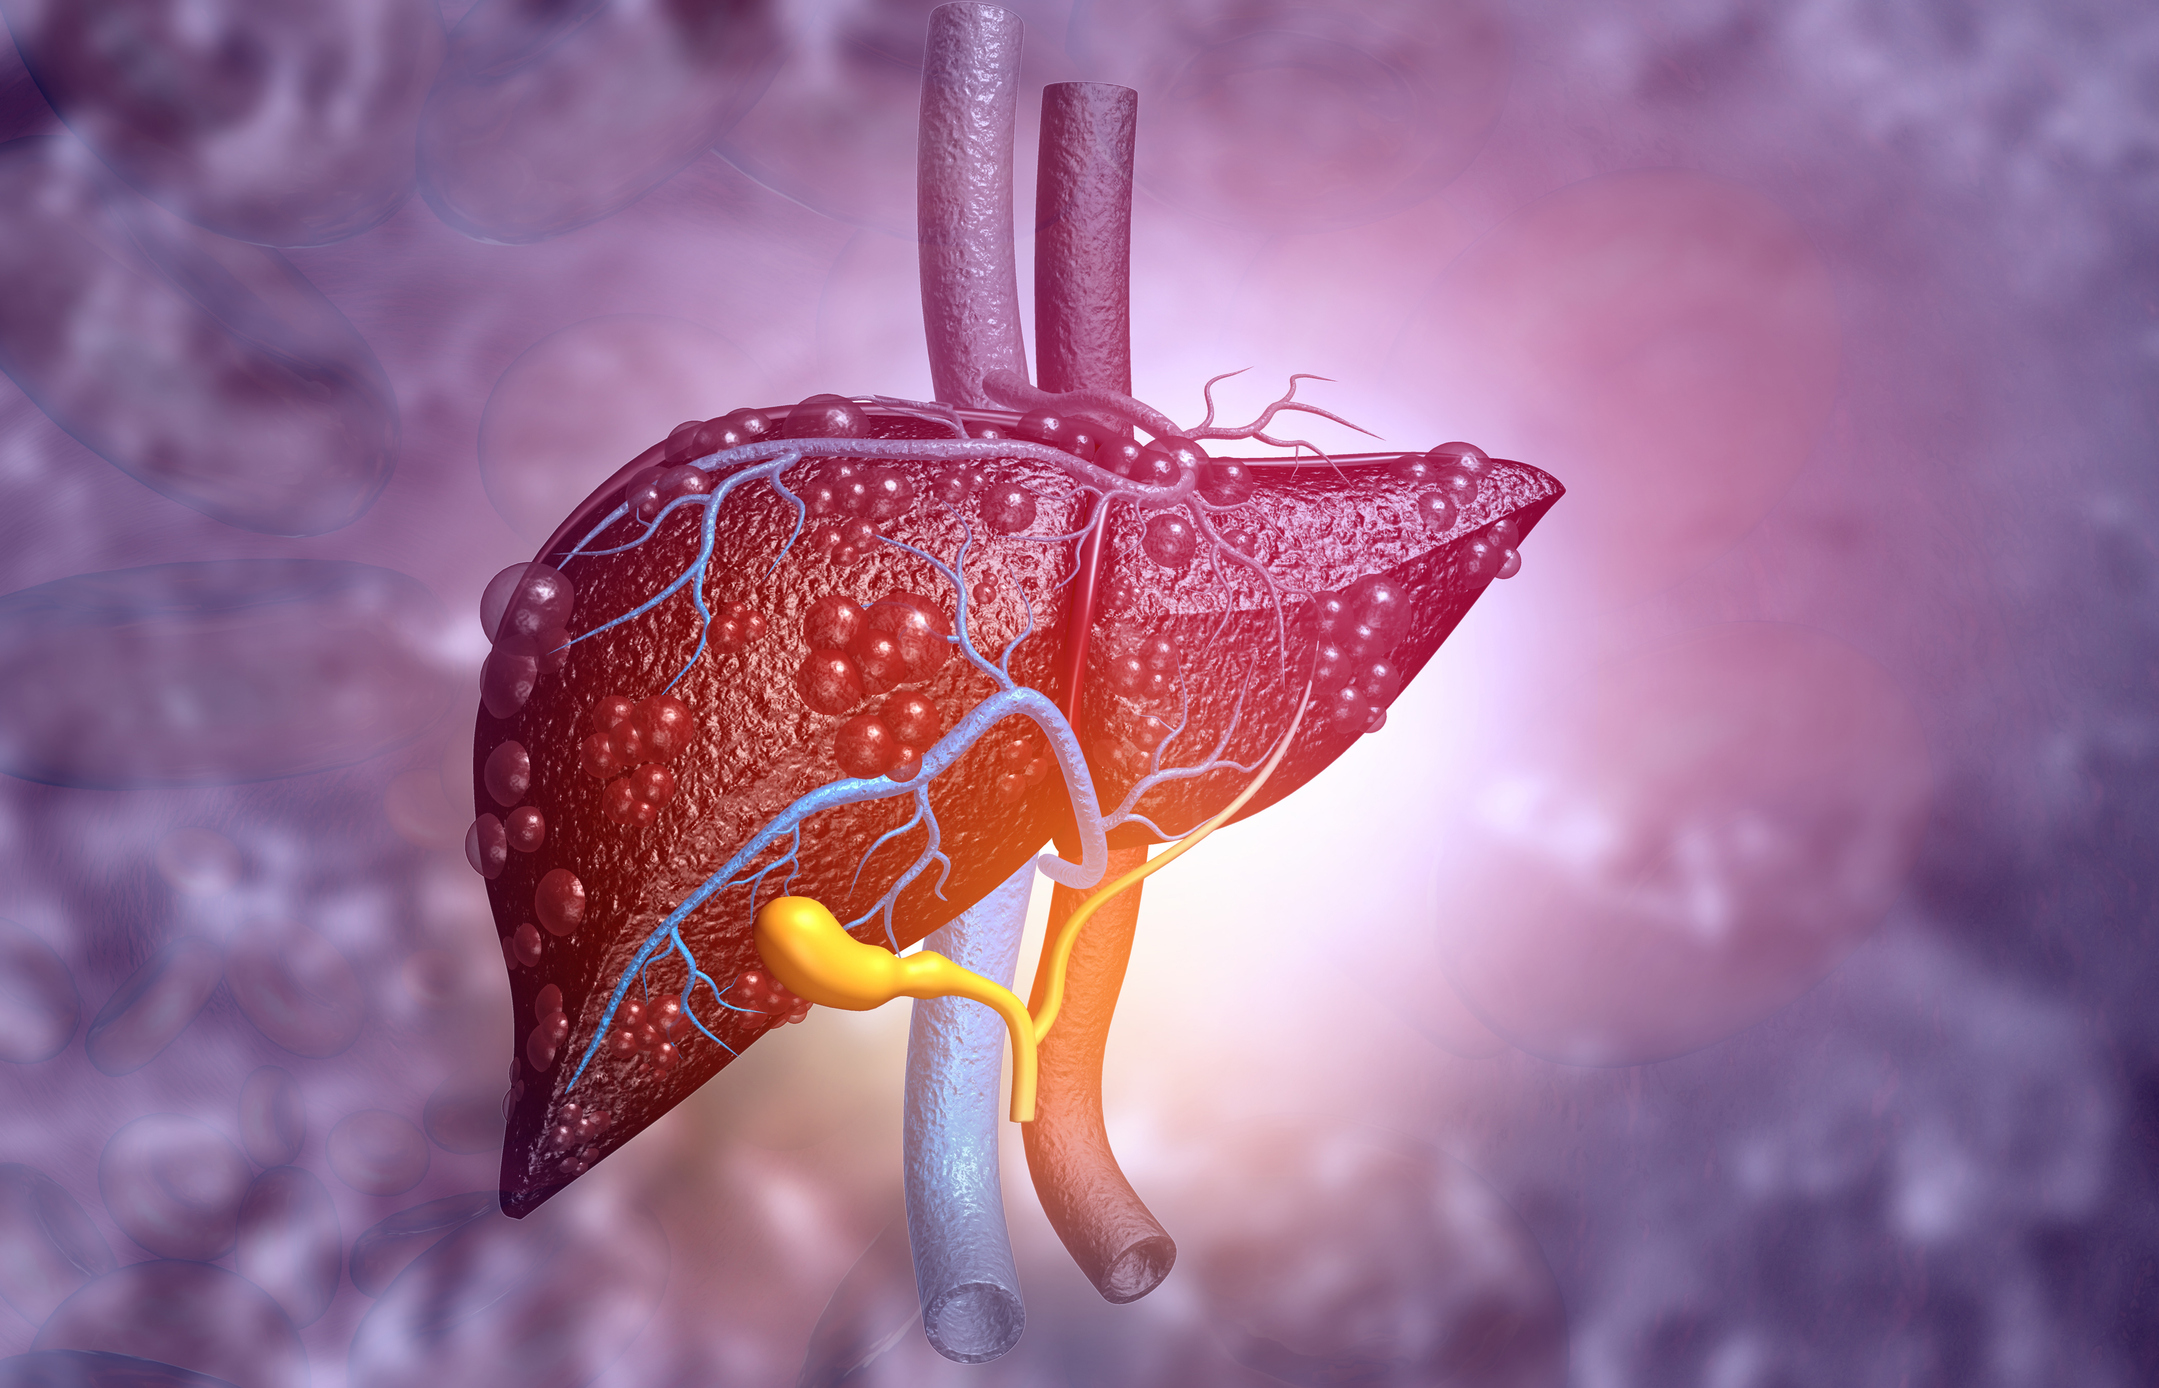

Postmenopausal women may be at risk for nonalcoholic fatty liver disease (NAFLD), a chronic condition caused by the build-up of excess fat in the liver not caused by alcohol. A review article by the Translational Genomics Research Institute (TGen) has suggested that these findings offer a new perspective on health risks for postmenopausal women. Nonalcoholic ...click here to read more